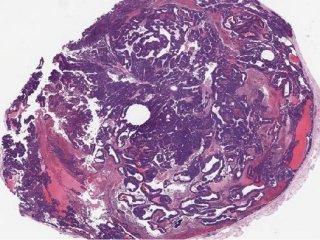

В перспективе модель войдет в систему поддержки принятия врачебных решений, которая позволит предоставлять оценку вероятности злокачественности опухоли и определять степень ее инвазии в соседние органы

Разработка позволит классифицировать опухоль и оценить уровень риска для пациента